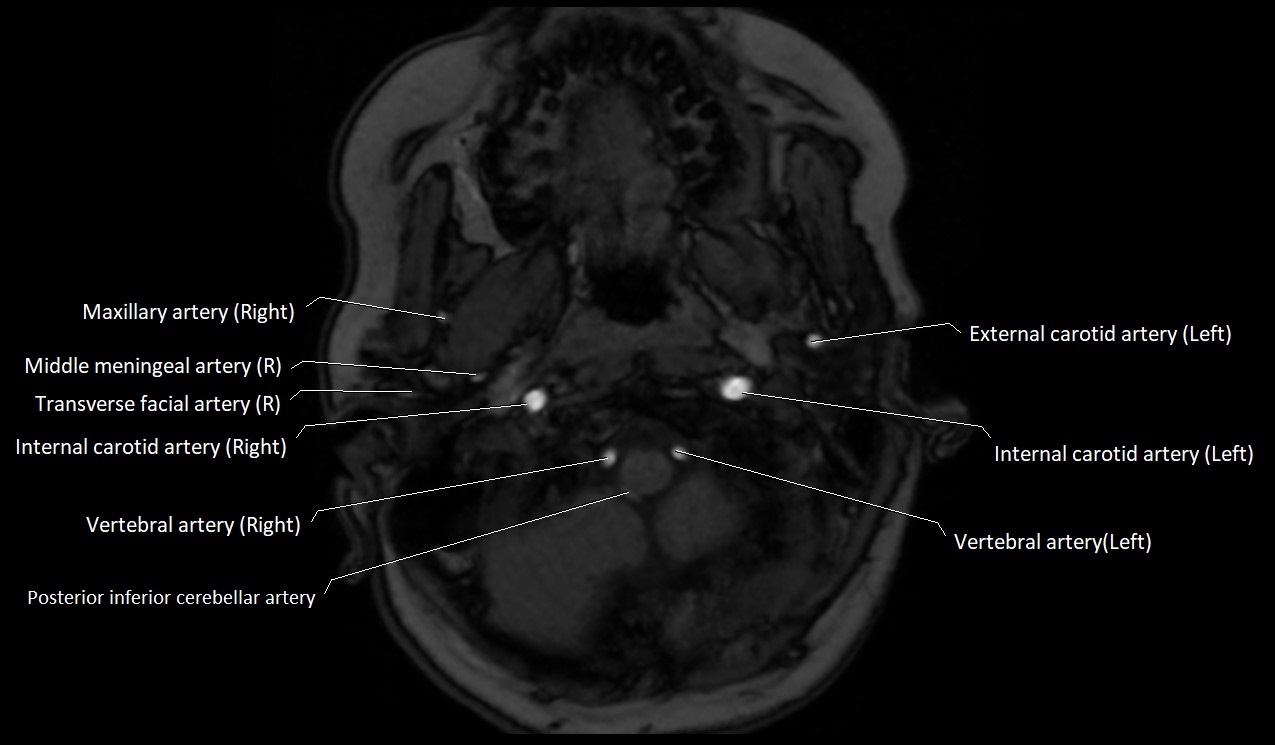

MRI images

image